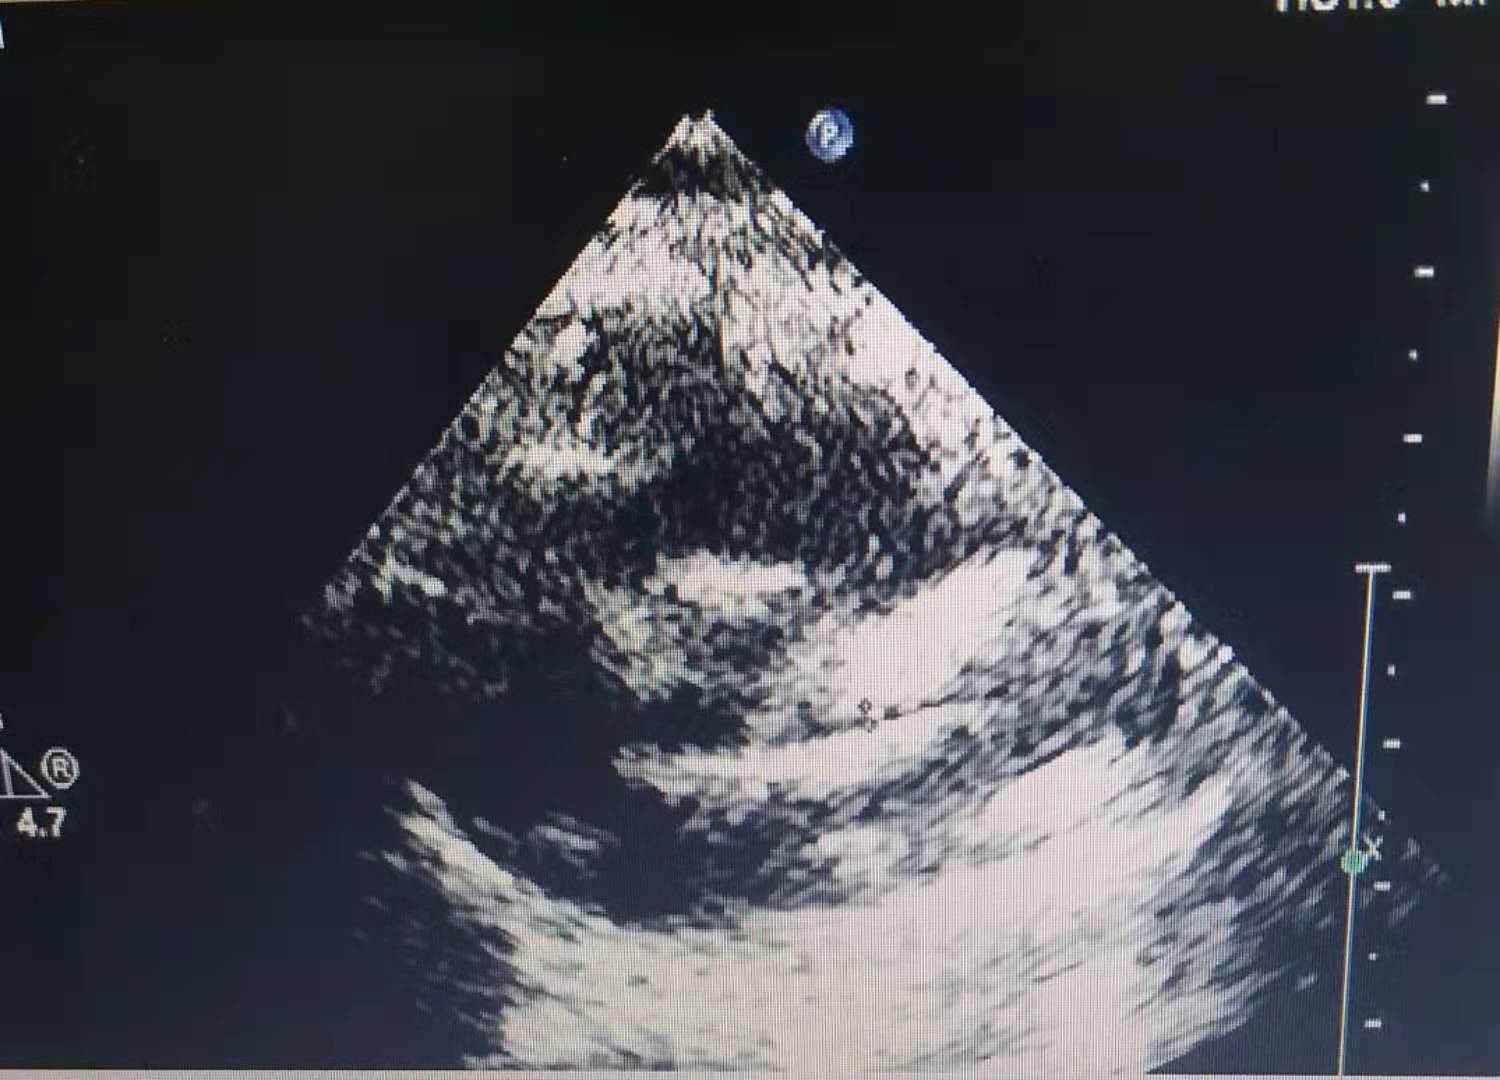

入院后赶紧完善各项相关检查,查新冠病毒核酸测定正常;流感A+B病毒抗原检测:阴性;血常规五分类:白细胞数目(WBC),17.66x10^9/L,H;中性粒细胞百分比(NEUT%),83.4%,H;淋巴细胞百分比11.6%,L;血红蛋白浓度(HGB),104g/L;血小板数目323x10^9/L,H;中性粒细胞绝对值14.72x10^9/L;外周血涂片异淋细胞2%;粪便常规+隐血试验:正常;血清C-反应蛋白(CRP),106.49mg/L,H;电解质六项、血清肌钙蛋白Ⅰ测定、轮状病毒未见异常;葡萄糖6-磷酸脱氢酶活性检测(G6PD),2662U/L ;降钙素原(PCT),0.959ng/ml,H。心脏彩超未见异常。EB病毒阴性。

第三天查房时患儿还是间中发热,但是低热为主,间隔时间明显延长,间中咳嗽、痰鸣、鼻塞,无抽搐,无明显气喘,解烂便,无伴黏液、脓血,精神、睡眠、饮食一般,小便可 。患儿病情好转,继续予抗感染、静注人免疫球蛋白治疗,予思连康调节肠道菌群失调,予阿司匹林抗血小板治疗,同时注意是否有指端、肛周脱皮,必要时复查心脏彩超了解冠状动脉是否扩张。